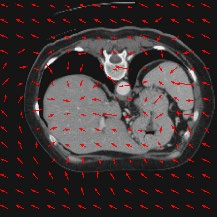

Transformers have made remarkable progress towards modeling long-range dependencies within the medical image analysis domain. However, current transformer-based models suffer from several disadvantages: (1) existing methods fail to capture the important features of the images due to the naive tokenization scheme; (2) the models suffer from information loss because they only consider single-scale feature representations; and (3) the segmentation label maps generated by the models are not accurate enough without considering rich semantic contexts and anatomical textures. In this work, we present CASTformer, a novel type of generative adversarial transformers, for 2D medical image segmentation. First, we take advantage of the pyramid structure to construct multi-scale representations and handle multi-scale variations. We then design a novel class-aware transformer module to better learn the discriminative regions of objects with semantic structures. Lastly, we utilize an adversarial training strategy that boosts segmentation accuracy and correspondingly allows a transformer-based discriminator to capture high-level semantically correlated contents and low-level anatomical features. Our experiments demonstrate that CASTformer dramatically outperforms previous state-of-the-art transformer-based approaches on three benchmarks, obtaining 2.54%-5.88% absolute improvements in Dice over previous models. Further qualitative experiments provide a more detailed picture of the model's inner workings, shed light on the challenges in improved transparency, and demonstrate that transfer learning can greatly improve performance and reduce the size of medical image datasets in training, making CASTformer a strong starting point for downstream medical image analysis tasks.